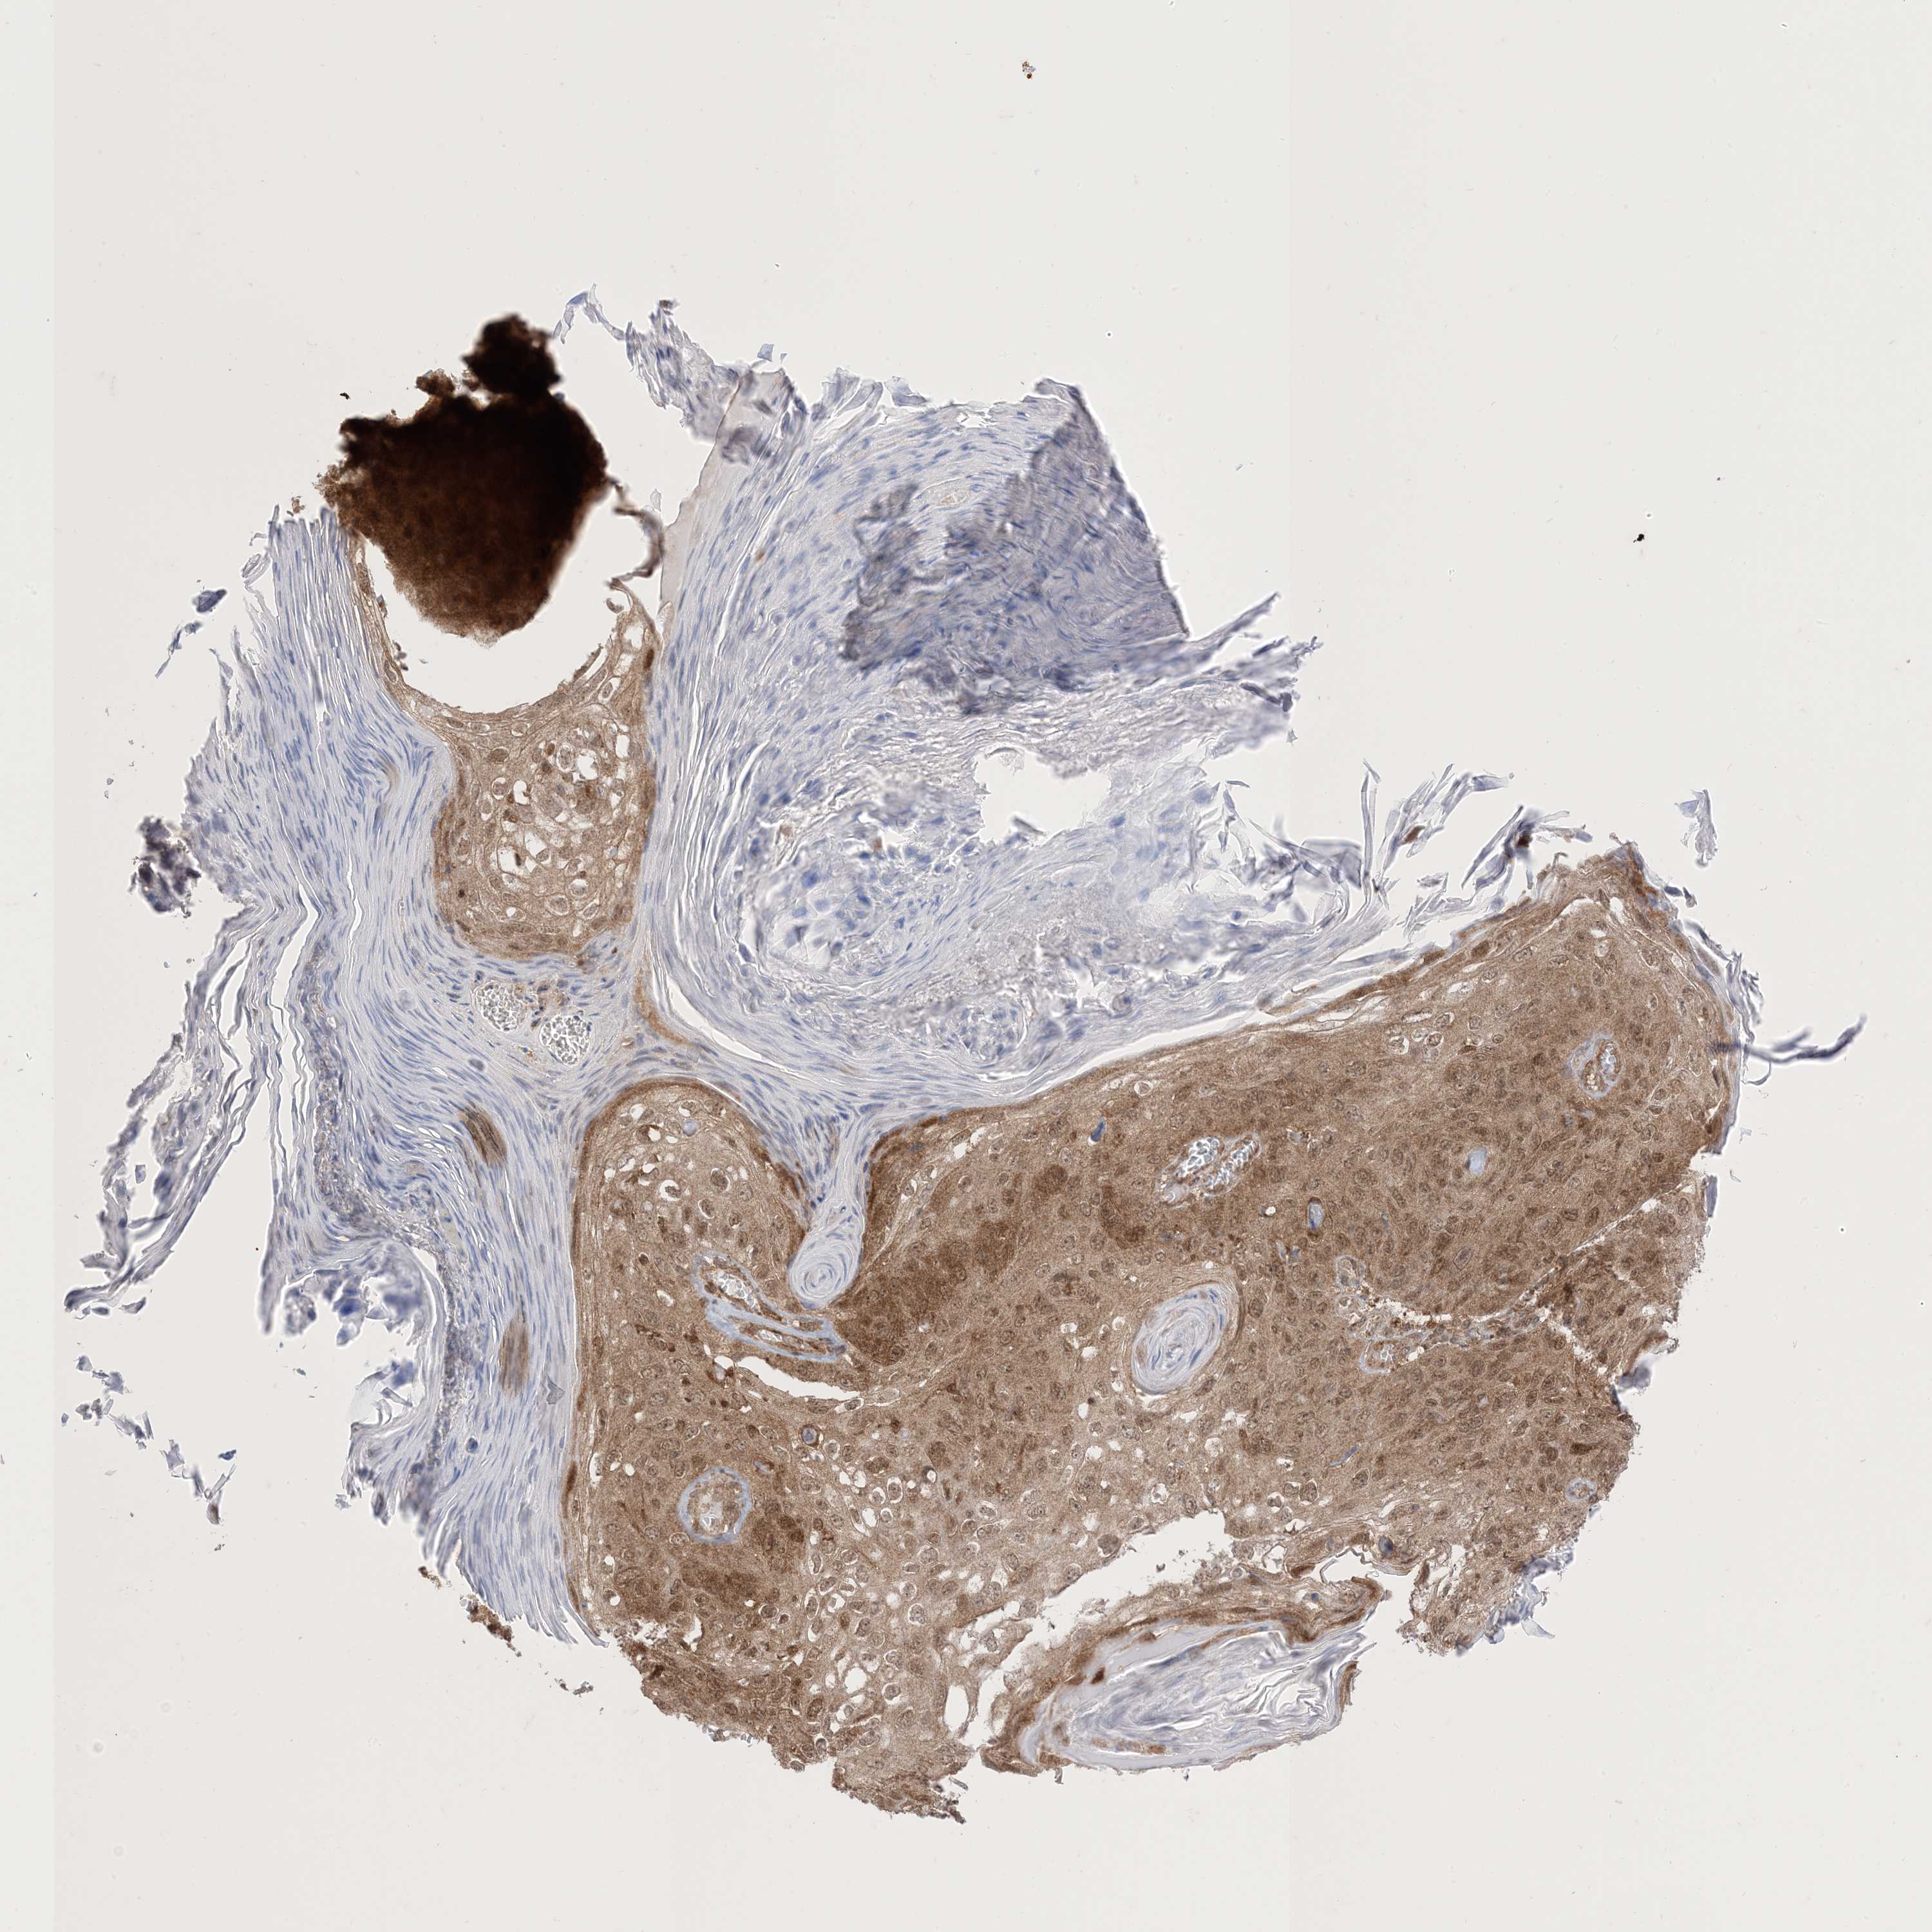

SKIN CANCER - Protein expressioni

A mouse-over function shows sample information and annotation data. Click on an image to view it in a full screen mode. Samples can be filtered based on level of antibody staining by selecting one or several of the following categories: high, medium, low and not detected. The assay and annotation is described here.

Antibody stainingi

Antibody staining in the annotated cell types in the current human tissue is reported as not detected, low, medium, or high, based on conventional immunohistochemistry profiling in selected tissues. This score is based on the combination of the staining intensity and fraction of stained cells.

Each image is clickable and will lead to virtual microscopy that enables deeper exploration of all samples and also displays staining intensity scores, fraction scores and subcellular localization as well as patient and tissue information for each sample.

HPA005695

Staining

High

Medium

Low

Not detected

Intensity

Strong

Moderate

Weak

Negative

Quantity

>75%

75%-25%

<25%

None

Location

Nuclear

Cytoplasmic/membranous

Cytoplasmic/membranous,nuclear

Basal cell carcinoma